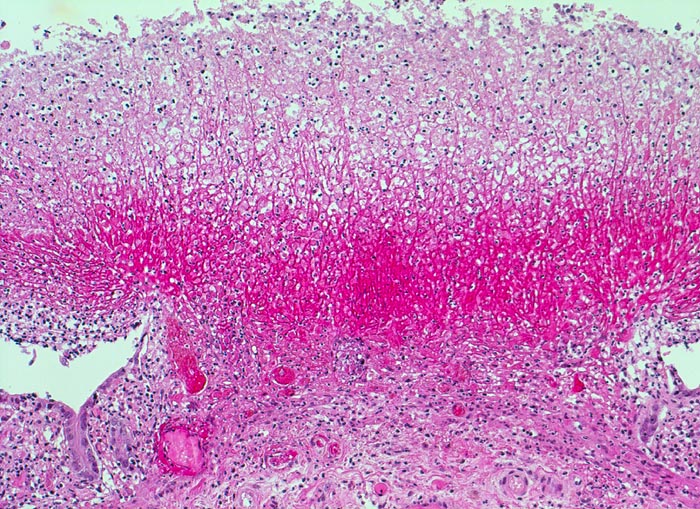

pseudomembranöse Kolitis

Pseudomembran aus roten Fibrinfäden, Detritus und Entzündungszellen auf einem oberflächlichen Schleimhautulkus. Die angrenzende erhaltene Mukosa zeigt einen Becherzellverlust und ein basophiles Epithel mit vergrösserten Kernen im Sinne einer ischämischen Schädigung.

Echte Membranen bestehen aus einem Epithel, deshalb der Ausdruck Pseudomembran für die Auflagerungen aus Fibrin, Detritus und Entzündungszellen bei der pseudomembranösen Kolitis.